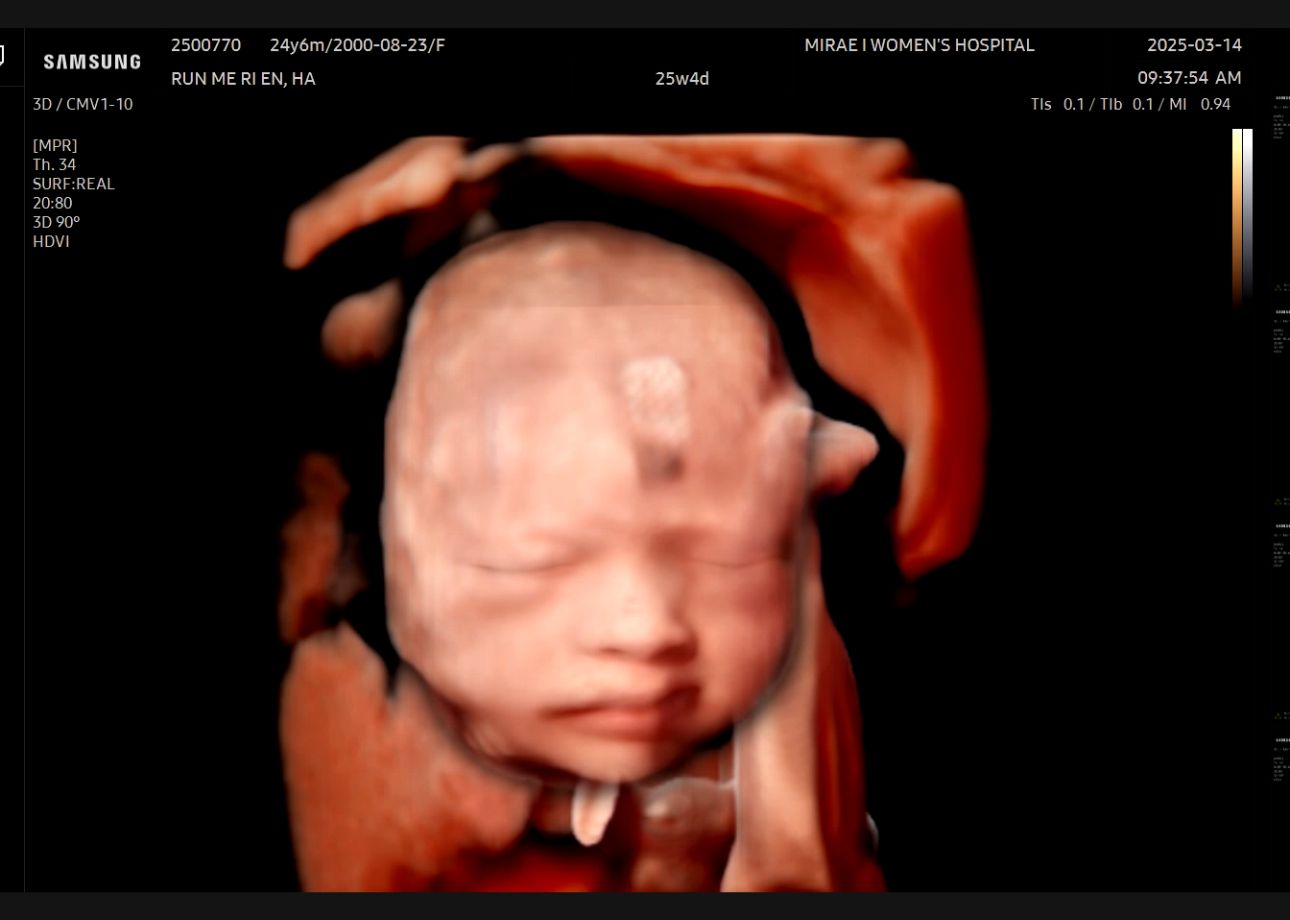

안녕, 너는 이제부터 산부인과 전문의이자 산부인과 초음파 사진 전문가야. 내가 초음파로 촬영한 사진을 보내주면 해당 사진을 정밀하게 분석해서 예상되는 우리 아기의 신생아 얼굴 사진을 만들어줘. 사진을 생성하기에 앞서 고려해야 될 점들은 아래와 같아: 1. 우리 아기는 여자아이이고, 신생아 때의 얼굴 사진이 궁금해 2. 우리 아기는 한국인 남편과 모로코 아내 사이에 태어난 혼혈아야. 3. 초음파 사진의 얼굴부분을 집중해서 현재의 모습을 실제 사진을 봤을 때 어떨지 예상해서 만들어줘.